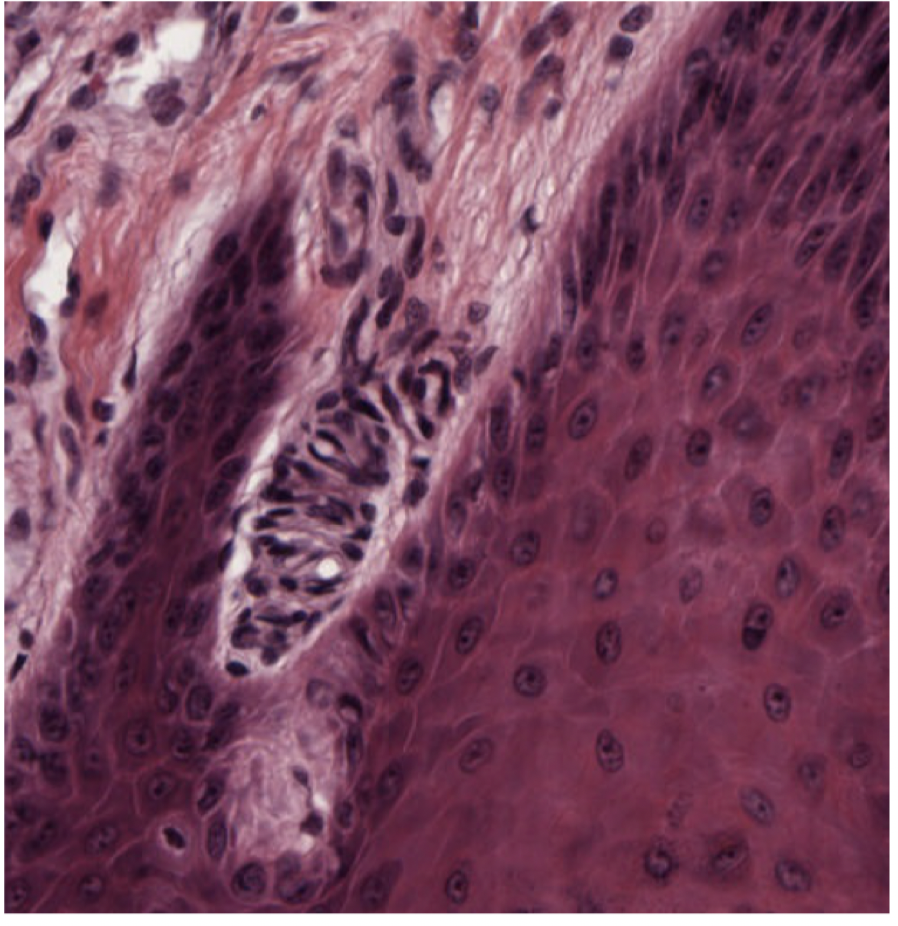

thick skin has a thick what

what is thick in thin skin